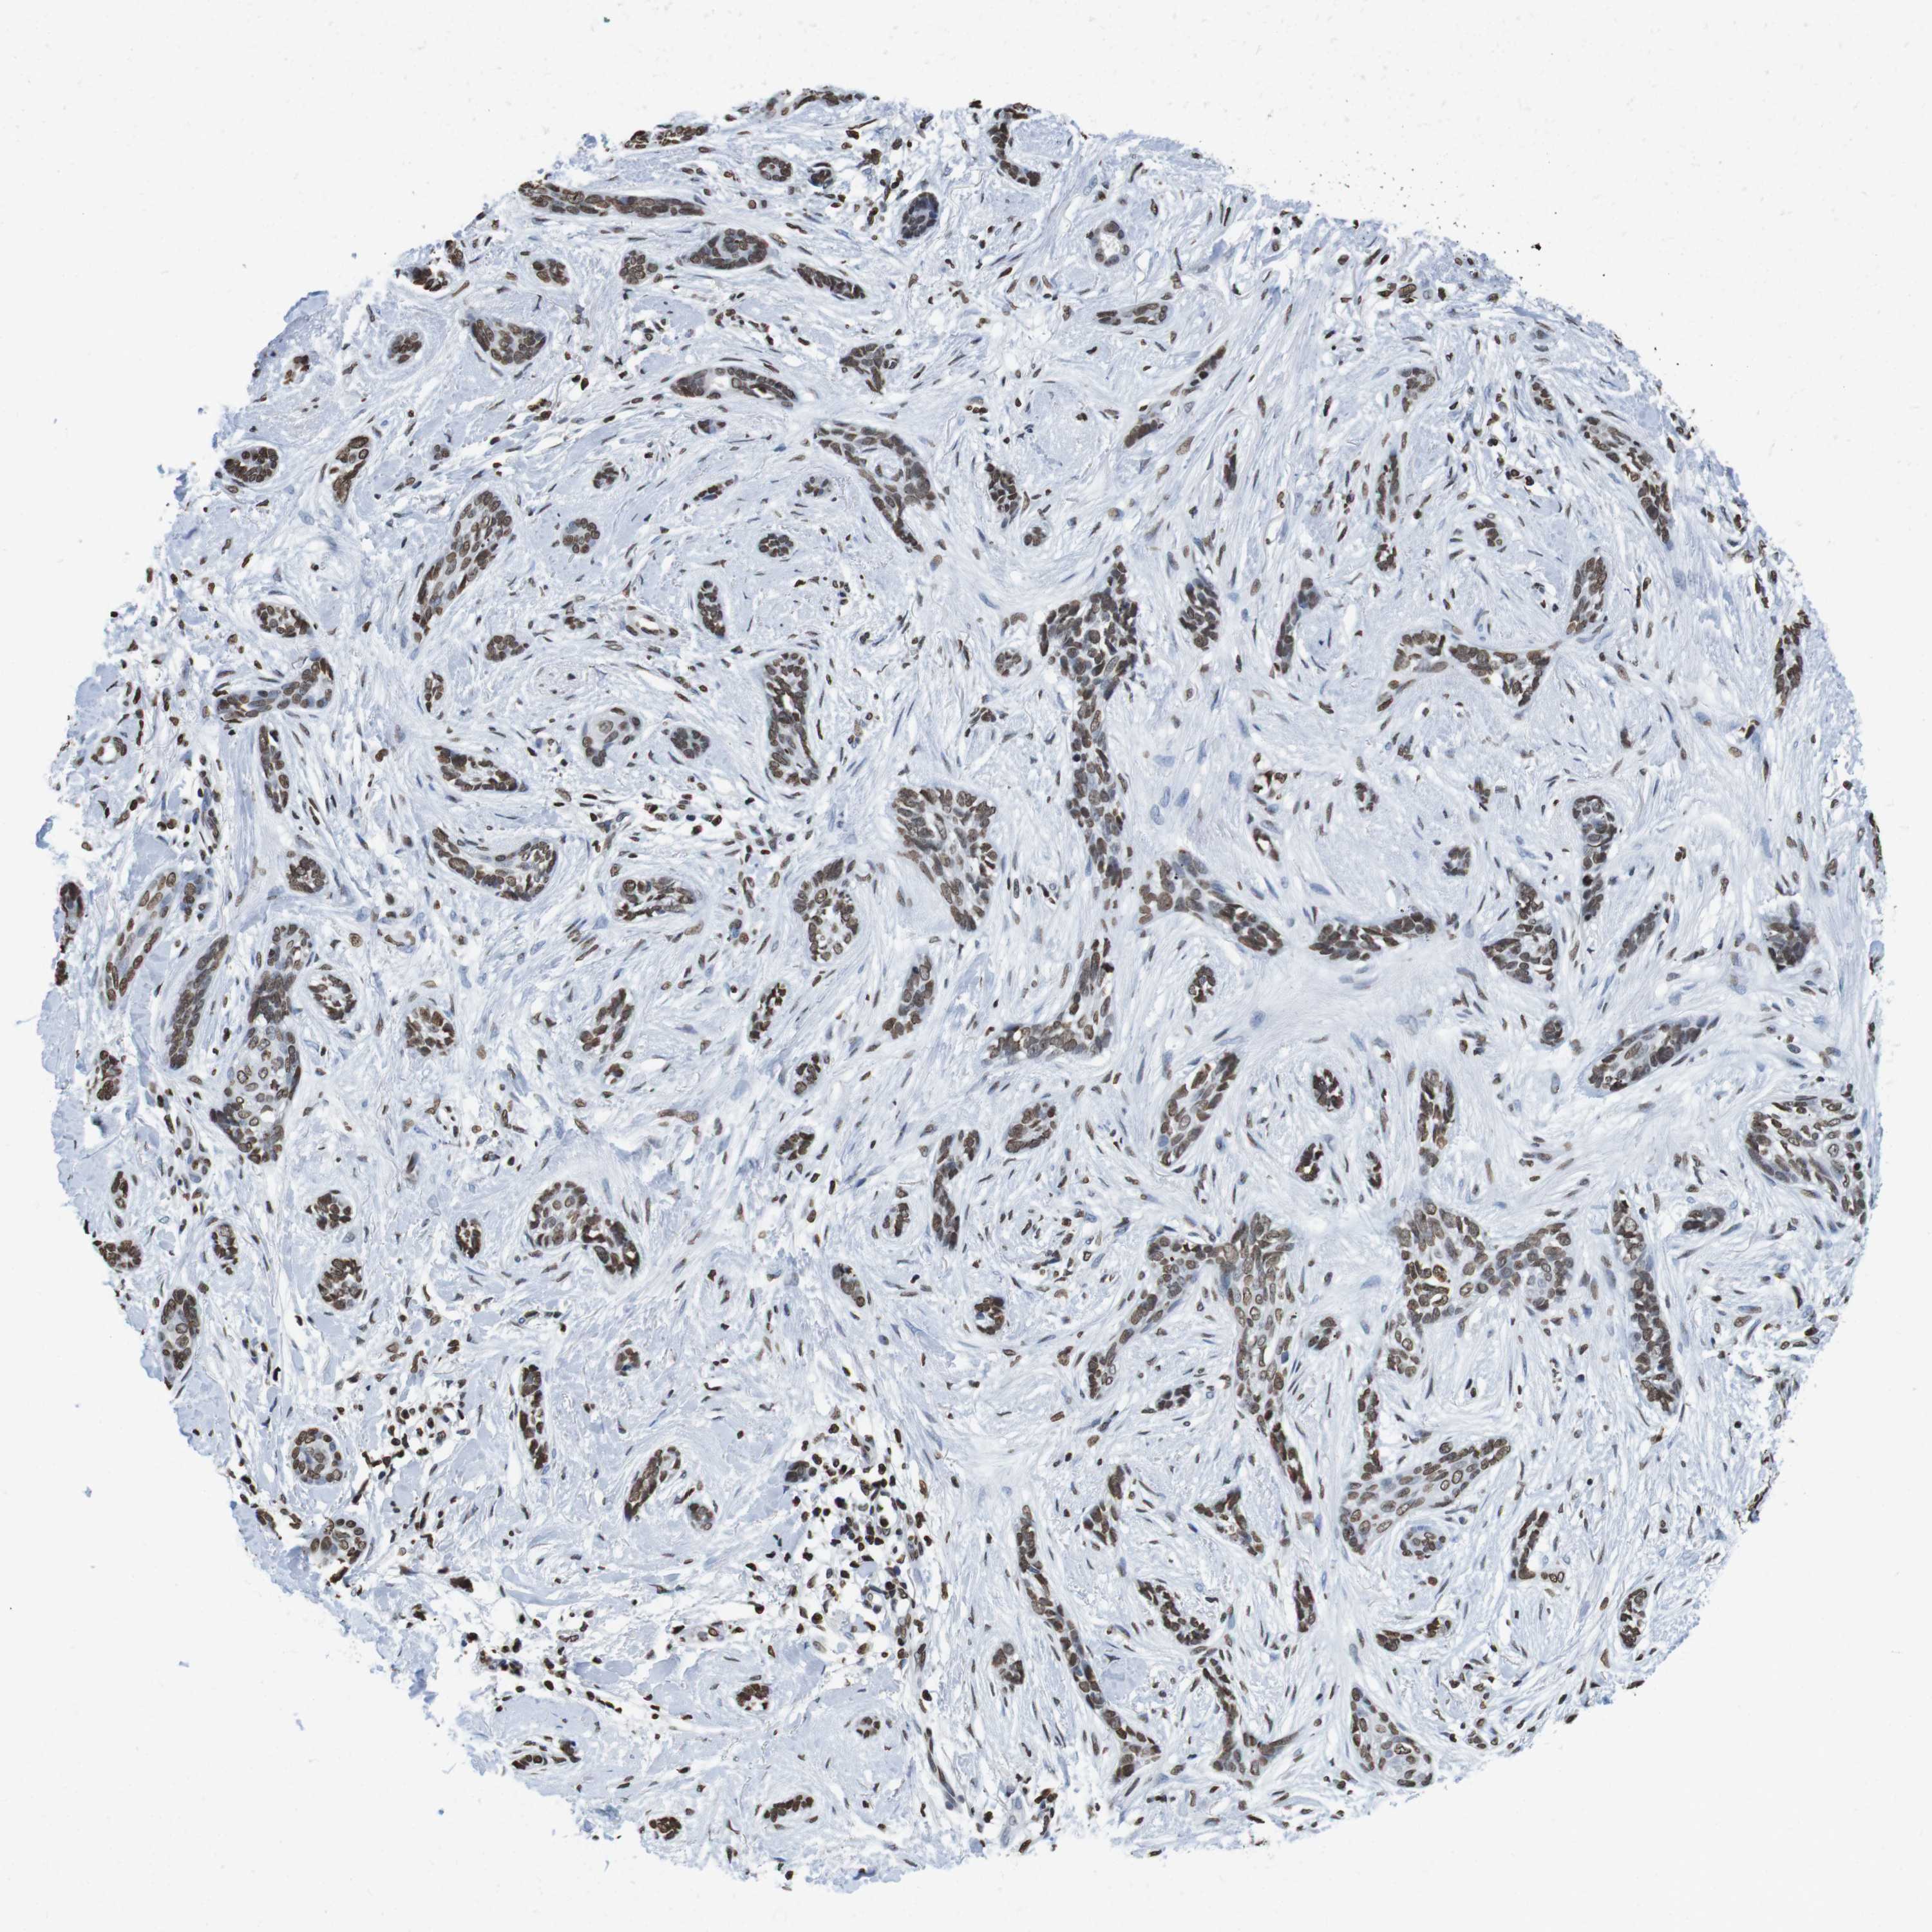

SKIN CANCER - Protein expressioni

A mouse-over function shows sample information and annotation data. Click on an image to view it in a full screen mode. Samples can be filtered based on level of antibody staining by selecting one or several of the following categories: high, medium, low and not detected. The assay and annotation is described here.

Antibody stainingi

Antibody staining in the annotated cell types in the current human tissue is reported as not detected, low, medium, or high, based on conventional immunohistochemistry profiling in selected tissues. This score is based on the combination of the staining intensity and fraction of stained cells.

Each image is clickable and will lead to virtual microscopy that enables deeper exploration of all samples and also displays staining intensity scores, fraction scores and subcellular localization as well as patient and tissue information for each sample.

Antibody HPA015654

Staining

High

Intensity

Strong

Quantity

>75%

Location

Nuclear

Squamous cell carcinoma in situ, NOS

Squamous cell carcinoma, NOS

Basal cell carcinoma

Adnexal tumor, benign